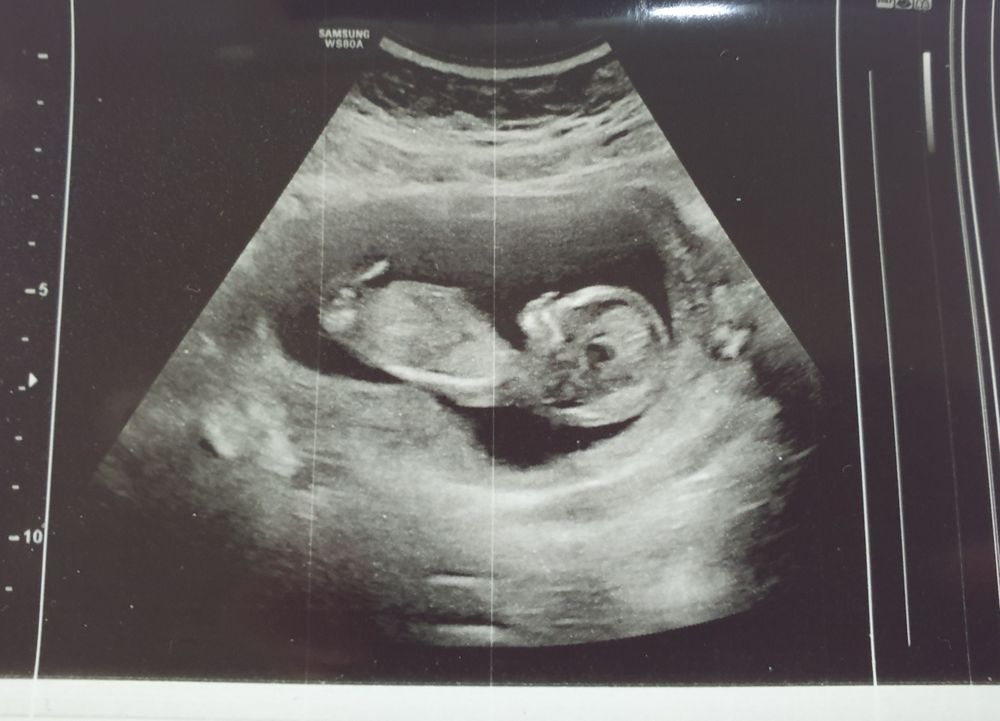

Здоровая беременностьНаконец - то пришло время, думала, что не дождусь этого волнительного момента 😍 Позавчера была на скрининге, по УЗИ у нас всё замечательно. Осталось дождаться результата по крови, но это только в четверг. Я настроена позитивно. 🤗 По КТР мы опережаем срок на неделю. По месячным 12 недель, а по узи 13 + 1. Интересно, почему так? И по какому сроку будут считать ПДР? Остальные показатели идеальные, кости носа визуализируются. Повода для беспокойства нет. 🙏🏻

Дали снимок, такой красивый малыш. Самый лучший. 🥰 Пол не сказали, но у меня такое чувство, будто это мальчик. Посмотрим, что скажут на втором скрининге.